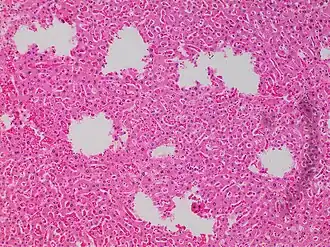

![Tearing artifacts, such as can be caused by: - Microtomy with a nick or blemish in the knife edge.[5] - Traction of the sections. - Too much or too little alcohol dehydration.[5] - Sectioning calcified parts, which can be decalcified or removed.[5]](./_assets_/Microscopy_of_liver_parenchyma_with_tearing_artifacts.jpg)